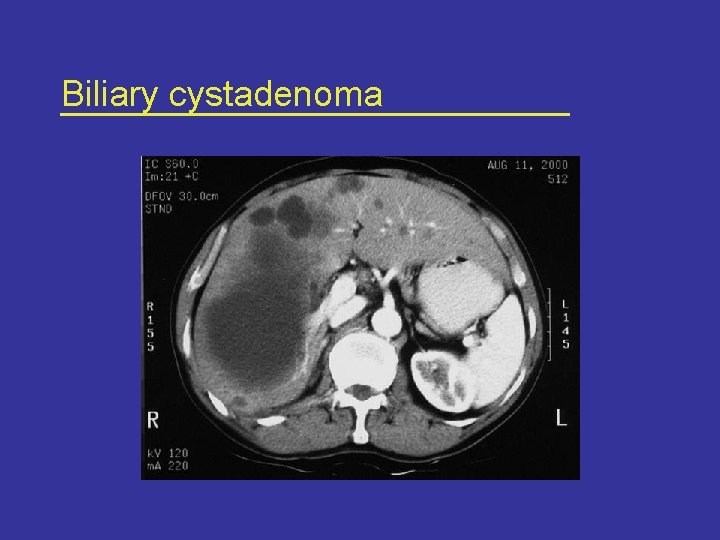

Radiological features • USG and CT are complementary* – – – Internal septations Thickened and irregular wall Mural nodules and papillary projections Calcifications Wall enhancement * Korobkin et al AJR Am J Roentgenol Sept; 153(3): 507 -11, 1989

Radiological features Ultrasonography CT scan

Biliary cystadenoma